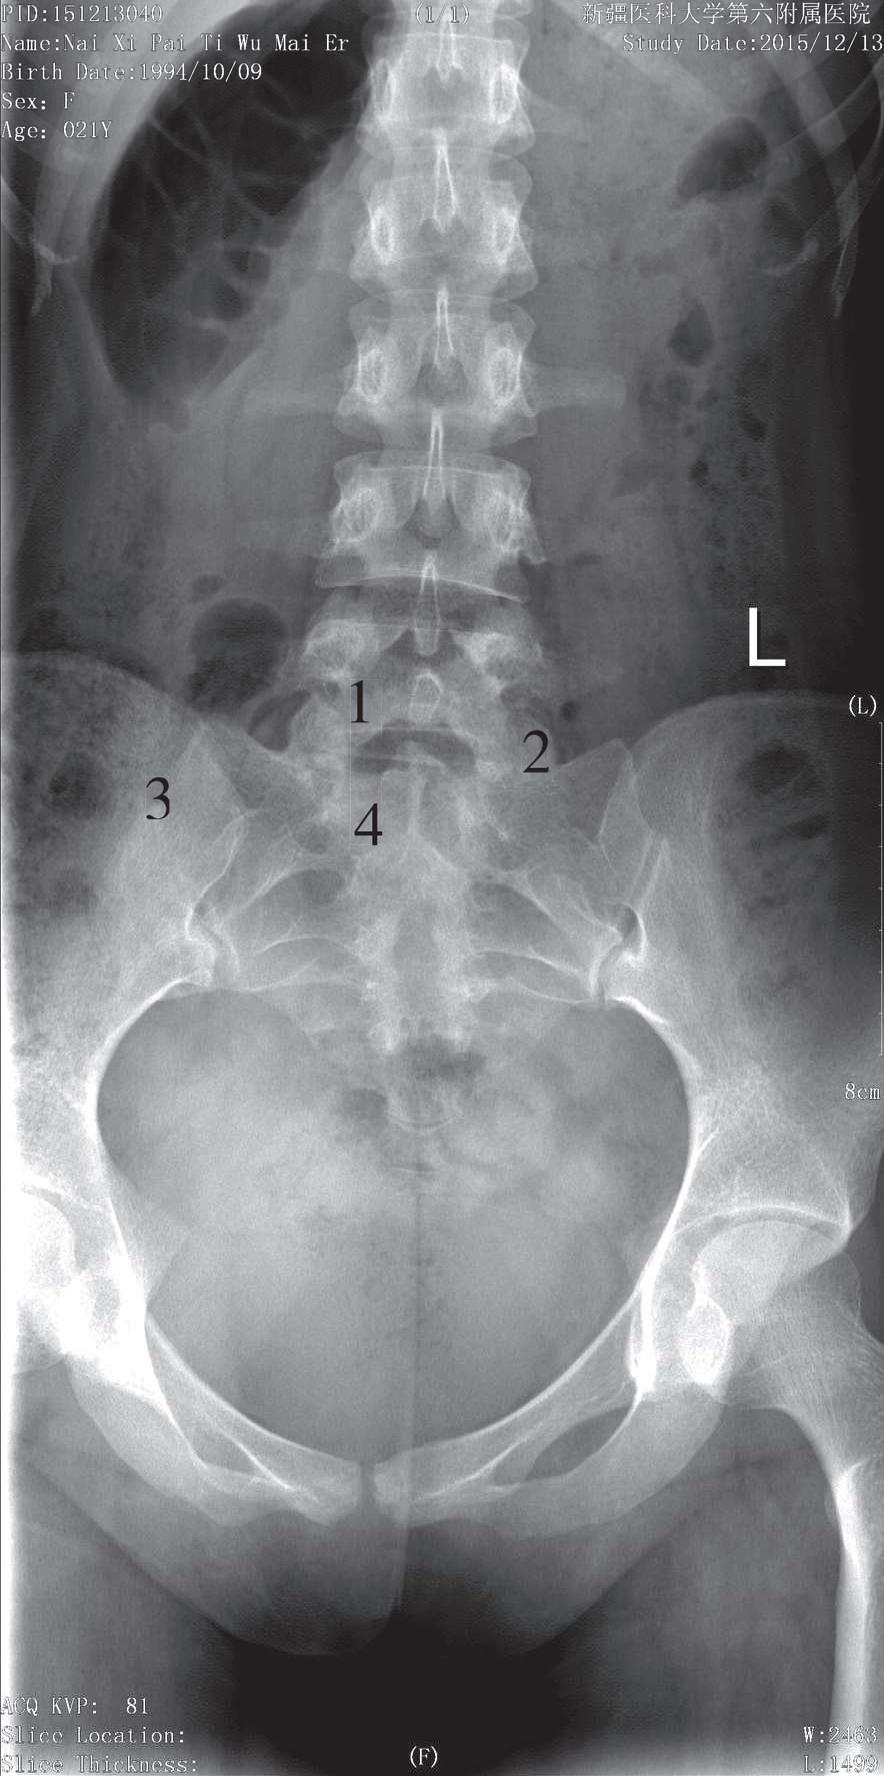

被检者仰卧于检查床上,两臂置于身体两侧,双下肢并拢伸直,身体正中矢状面与影像接收器中线重合,上缘包括L 4 ,下缘包括耻骨联合下缘3cm。骶骨摄影时中心线向头侧倾斜15°~20°,经耻骨联合上缘3cm处射入;尾骨摄影时中心线向足侧倾斜15°,经耻骨联合上缘3cm处射入。影像分别显示骶骨、尾骨正位像,骶正中嵴位于影像中央,骶、尾骨骨质结构清晰,骶孔左右对称,无肠容物干扰(图3-17)。

1. L 5 ;2. 腰骶关节;3. 骶髂关节;4. S 1 椎体

图3-17 骶尾骨前后位片